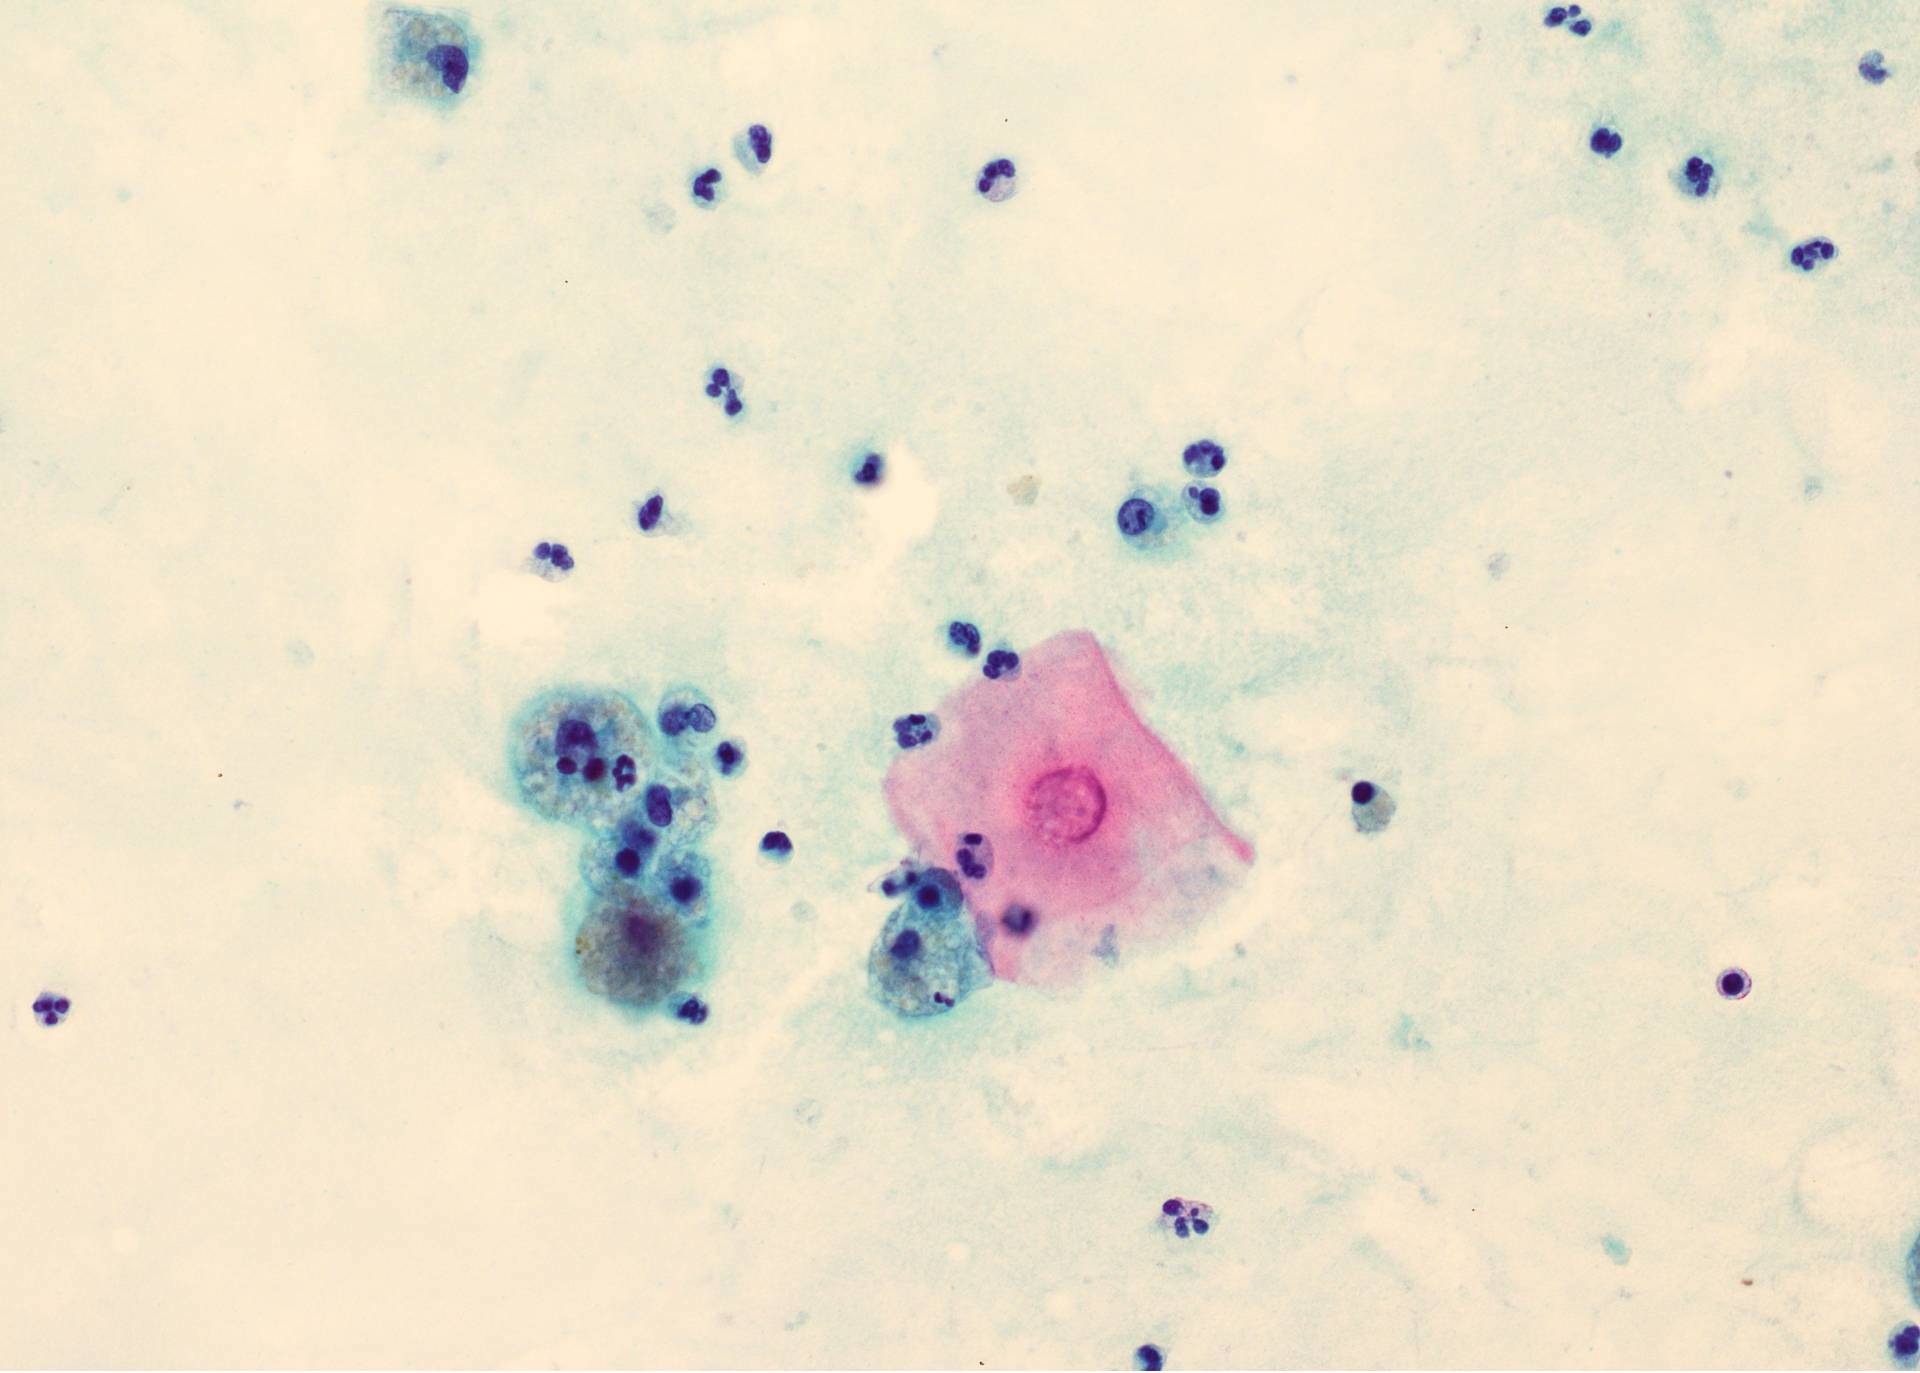

Cytology description

- Preoperative FNA is moderately sensitive but with many false negatives (Diagn Cytopathol 2005;33:365)

- FNA smears are of low cellularity, with predominant inflammatory cells outnumbering epithelial cells, similar to branchial cleft cyst:

- Macrophages, either foamy or hemosiderin laden

- Mature lymphocytes and neutrophils (predominantly if the cyst is infected)

- Squamous or ciliated columnar epithelium

- Colloid is common, ranging from thick and fragmented to thin and watery

- Admixture of cholesterol crystals

- Thyroid tissue found in < 10% of aspirates, likely due to deep embedding in the cyst wall

Cytology images

Contributed by Andrey Bychkov, M.D., Ph.D., Ayana Suzuki, C.T., Ram Kumar Kurpad R, M.B.B.S., M.D. and Y. C. Spoorthy Rekha, M.B.B.S., M.D.

Images hosted on other servers: